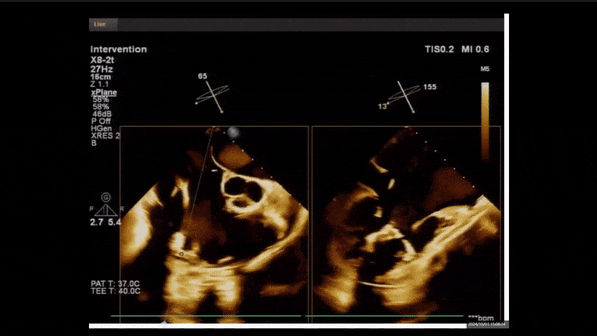

術(shù)前TEE評估

1、3D TEE顯示雙房及右室擴大,右室中段直徑40mm,右室FCA 52%。三尖瓣環(huán)TAPSE 22mm,三尖瓣環(huán)左右徑49mm,三尖瓣隔葉長度16mm,前葉長度21mm,后葉長度34mm,三尖瓣前隔gap 11mm,后隔gap 5.6mm,AP gap 12mm,診斷極重度功能性三尖瓣返流(Type I型三尖瓣:Torrential FTR 5+)。

2、彩色多普勒顯示:收縮期三尖瓣口返流束起源于后隔交界、前后葉之間及前隔交界,返流束縮流頸最大寬度27mm,三尖瓣返流口EOA=2.02cm2,返流容積124ml,收縮期三尖瓣返流峰值速度2.64m/s,返流峰值壓差28mmHg,PAPs 43mmHg,舒張期三尖瓣口平均跨瓣壓差1mmHg,肝左靜脈可見明顯逆向血流波。

術(shù)中經(jīng)食道超聲輔助下可見LuX-Valve Plus夾持件抓捕瓣葉狀態(tài)良好,夾持件在位,室間隔錨定位置良好,假體瓣膜整體錨定狀態(tài)穩(wěn)固。